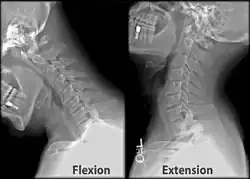

The movement of nodding the head takes place predominantly through flexion and extension at the atlanto-occipital joint between the atlas and the occipital bone. However, the cervical spine is comparatively mobile, and some component of this movement is due to flexion and extension of the vertebral column itself. This movement between the atlas and occipital bone is often referred to as the "yes joint", owing to its nature of being able to move the head in an up-and-down fashion.

The movement of shaking or rotating the head left and right happens almost entirely at the joint between the atlas and the axis, the atlanto-axial joint. A small amount of rotation of the vertebral column itself contributes to the movement. This movement between the atlas and axis is often referred to as the "no joint", owing to its nature of being able to rotate the head in a side-to-side fashion.

X-ray of cervical spine in flexion and extension -